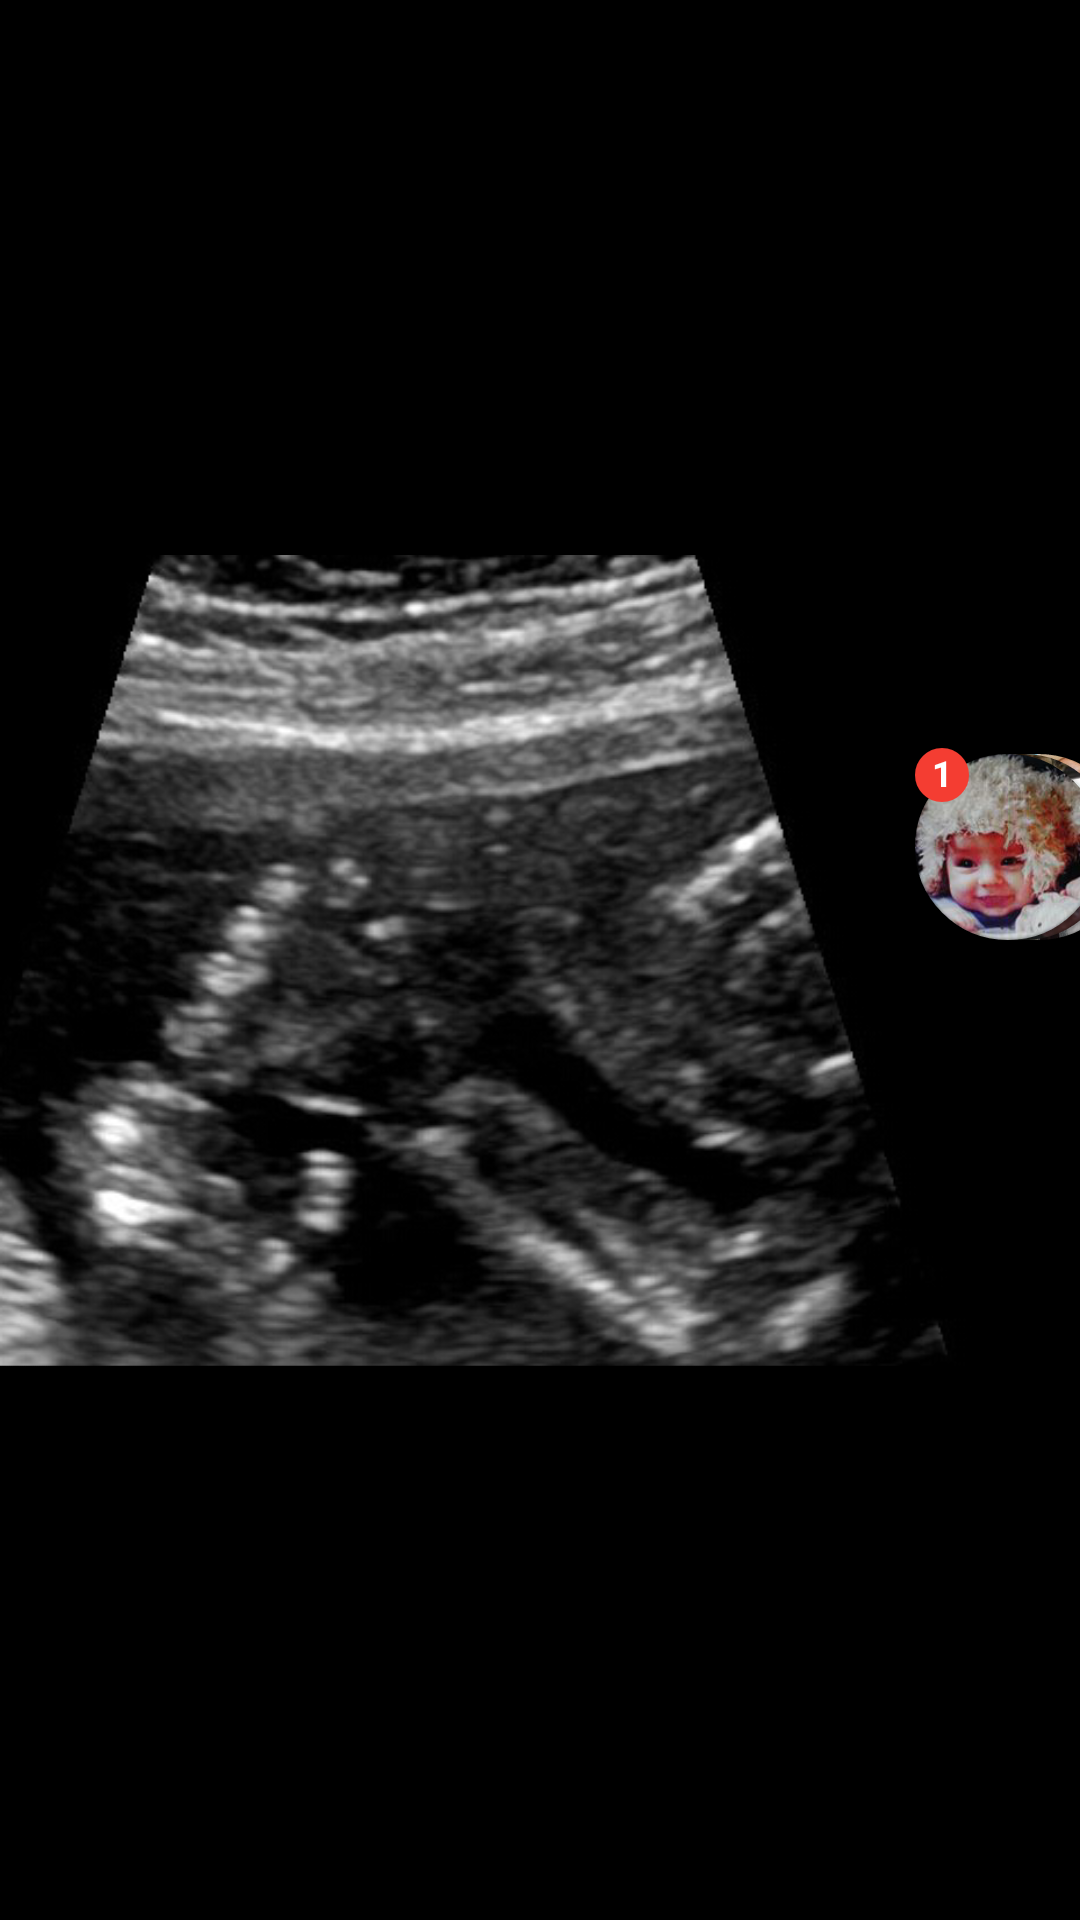

Hello! Wierd question after my scan yesterday. Do you think if a baby had six fingers the tech would include the handprint pic without telling you? Or tell yoy everything looked.good? I was nervous during the scan so she told me nothing to worry about even though she isn't supposed too...which was nice. But now looking at the disc of picture she gave me the hand one looks like it has six. Fingers..but I feel like she wouldn't put it on the disc if there was something wrong? A lady at work and I counting the fingers for fun and both felt it looked like six but maybe the thumb was bent so looked like 2. Any experience with this?

• No Noone has that..I just heard of it today from googling. Apparently it's common. Here is the pic..I am starting to think it's a fist maybe and two bones in the thumb? But then I'm worried about his hand being a fist bc I heard that's bad.  They shouldn't give these tjings to hylochonfriacs without immediate explanations..I drive myself crazy.

• I'm not trained but that appears to be the joint of the thumb to my naked eye. If your concerned though talk to your dr. I'm sure he or she has 5 fingers or they would have told you. :)

• I don't see any extra fingers. I'm in no way an expert, but I don't see anything to worry about. Also, I don't know how you could tell if it's in a fist - the fingers still have some growing to do

• I'm not trained either but it looks pretty normal to me too.

• Looks like a joint in the thumb to me, stop stressing yourself out!

• That looks like one of two things to me, either a thumb joint or a part of the placenta.  Too close to tell but they would not have given you this picture if it were abnormal.

Since my baby has DS they spent a lot of time looking at her fingers and joints to make sure she had all 3 bones in her pinky fingers (DS marker if they are missing a joint). Like others have said, this looks like the separate bones in her thumb! Looks just like the picrure out tech showed us when she saw that all the correct bones were present :)

• It looks like the thumb is bent and you can see both joints and the fingers are curled.

My husband initially saw 6 fingers when we were looking at the hands and after he pointed it out I saw it too! The tech counted through each digit, revealing 5 on each hand (and she pulled up toes for good measure). If she hadn't gone through each of the fingers I would have been convinced he had six. Ultrasounds can be very hard to read for those of us who aren't trained on them.

• Haha Tha KS guys..I caved and called the hospital..the report was done and she said it was all normal..so that must be a thumb joint or something. To the girl that mentioned the princess bride...haha I was thinking that the whole time because my boyfriend suggested calling the baby (joking) inigo  the day before I got the scan...haha I thought it was a bad sign